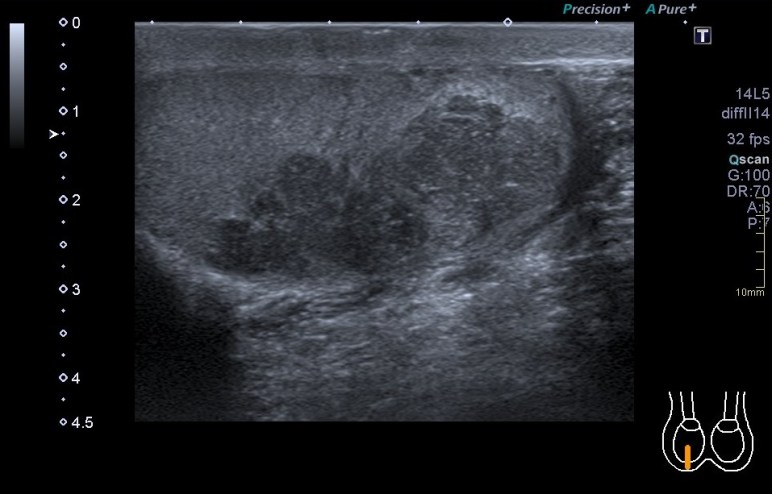

En el final del protocolo tenemos el infraespinoso. En relación con este corte te voy a contar que es un corte donde estudiamos en normalidad, articulación glenohumeral, labrum posterior (triangular e hiperecogénico), músculo infraespinoso como puedes ver en las dos imágenes siguientes, donde existe normalidad en la primera y donde coexiste la anatomía con la patología por la ausencia del labrum, sustituido por una buena cantidad de líquido justo en la articulación glenohumeral.